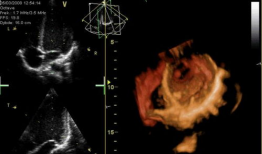

心脏跳动的视频,揭秘心脏跳动的奥秘

你知道吗?最近在网上流传着一个特别神奇的视频,它记录了心脏跳动的瞬间。这可不是普通的视频,它让我们仿佛能感受到心跳的力量,那种感...